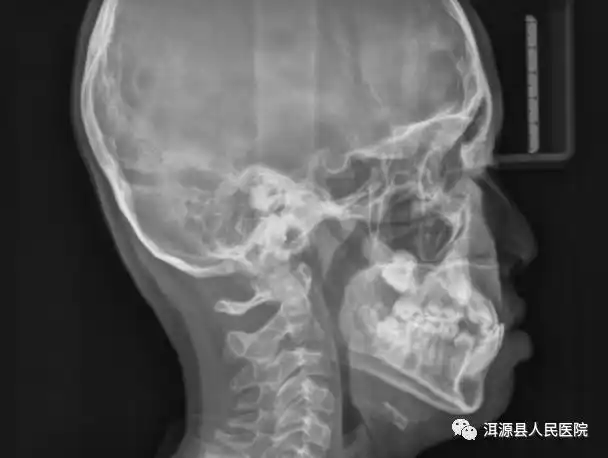

(图 4 头颅正侧位片)既往就医(普外科)2016 年 2 月患者因「腹胀腹痛

在给阿姨拍了个全身骨头的x光片后,阿姨和家人吓了一跳,张阿姨的头颅